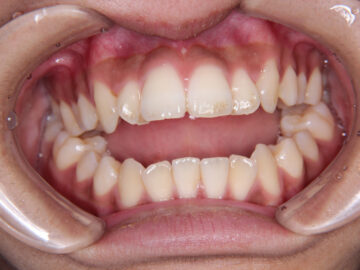

開咬(顎位不安定・自費治療・クリアタイプブラケット)

16歳 男性

ご相談時

小学生の頃は上下の前歯が当たっていたのに、今は上下の前歯が咬みあわない。